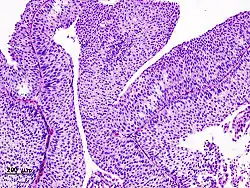

| Histopathology of transitional carcinoma of the urinary bladder. Transurethral biopsy. Hematoxylin and eosin stain. | |